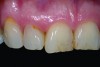

A 60-year-old female presented with worn incisal edges, discoloration among her maxillary teeth, and a reverse smile line that did not follow the curve of her lower lip (Figure 1). She also demonstrated receding gingiva on tooth No. 10 that created gingival disharmony in her smile. She was displeased with the overall appearance of her anterior teeth. However, the patient was uninterested in pursuing the more invasive surgical and restorative recommendations she had received from other dentists (ie, tissue graft, extraction, implant placement) that would have balanced the gingival display throughout the esthetic zone. She was opposed to removing any more tooth structure than was necessary, and her primary concern was for correcting the appearance of teeth Nos. 8 through 10.

Fig 1. Preoperative view of the patient

Figure 1